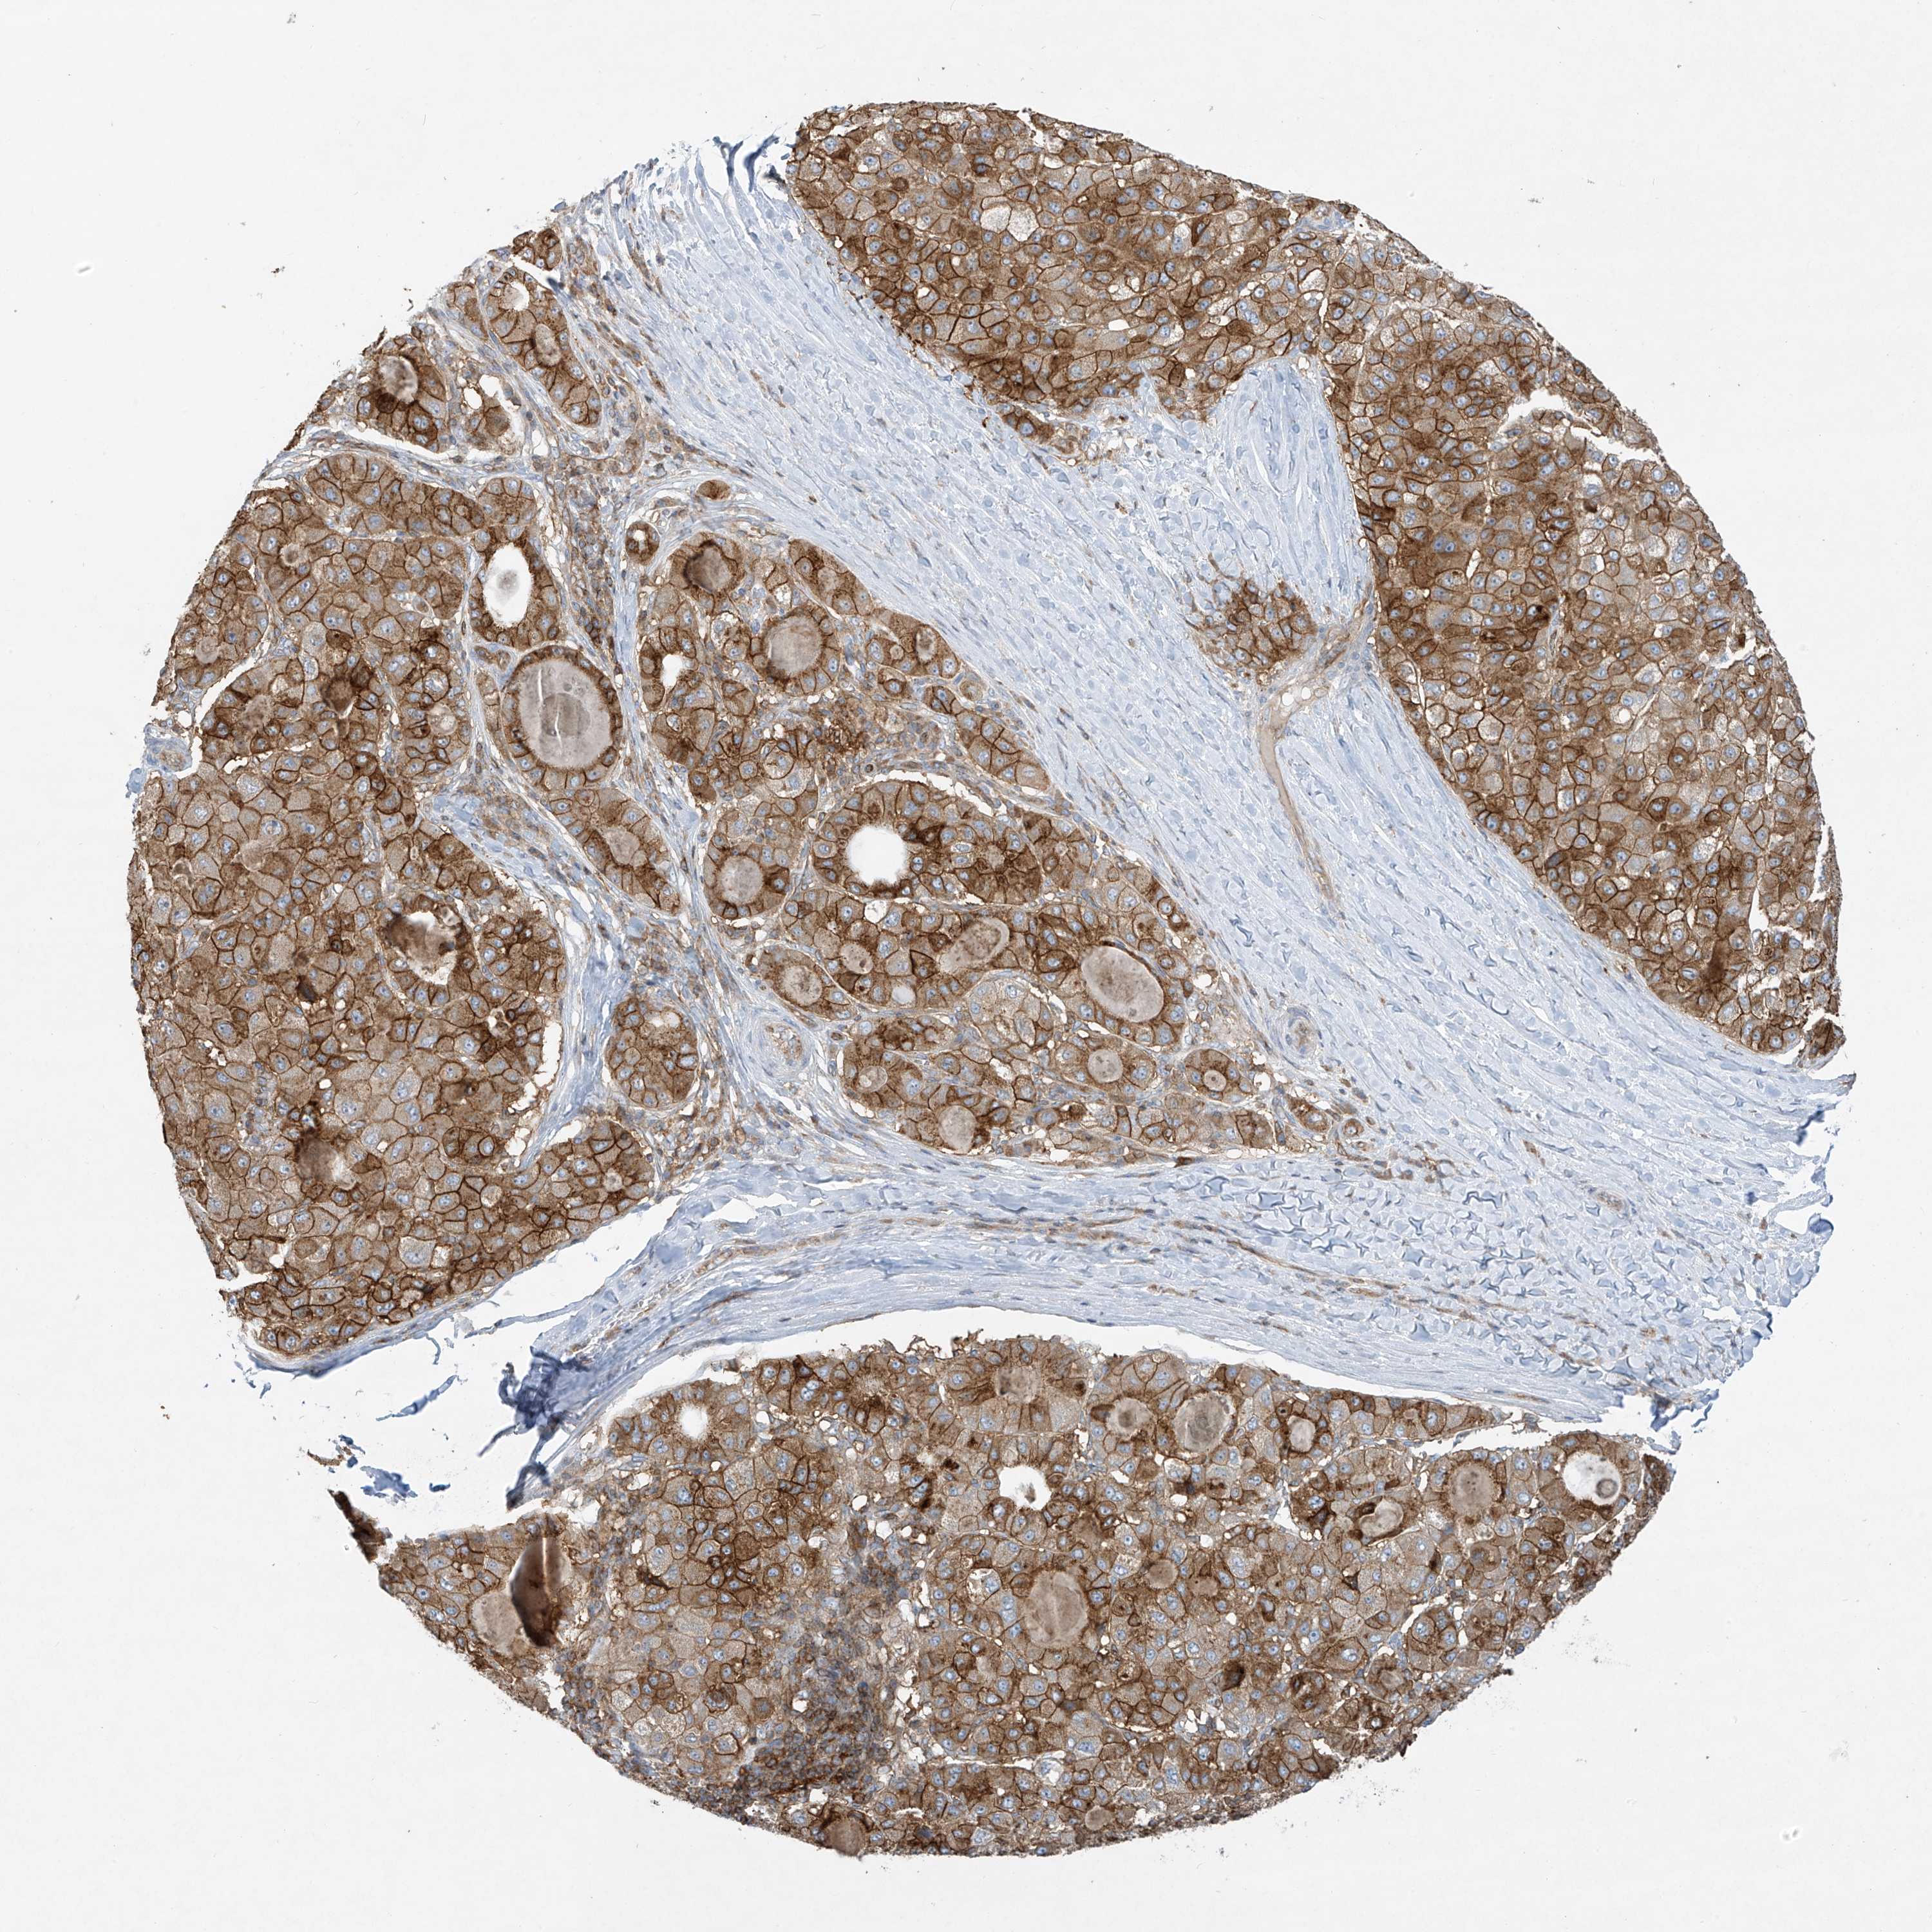

LIVER CANCER - Protein expressioni

A mouse-over function shows sample information and annotation data. Click on an image to view it in a full screen mode. Samples can be filtered based on level of antibody staining by selecting one or several of the following categories: high, medium, low and not detected. The assay and annotation is described here.

Note that samples used for immunohistochemistry by the Human Protein Atlas do not correspond to samples in the TCGA dataset.

Antibody stainingi

Antibody staining in the annotated cell types in the current human tissue is reported as not detected, low, medium, or high, based on conventional immunohistochemistry profiling in selected tissues. This score is based on the combination of the staining intensity and fraction of stained cells.

Each image is clickable and will lead to virtual microscopy that enables deeper exploration of all samples and also displays staining intensity scores, fraction scores and subcellular localization as well as patient and tissue information for each sample.

Antibody HPA031454

Antibody CAB024589

Cholangiocarcinoma

Carcinoma, Hepatocellular, NOS